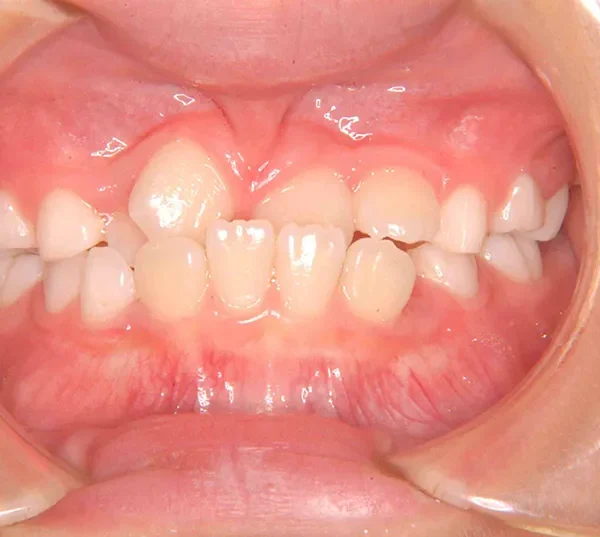

初診時年齢 小学校2年生 (女性) 主訴 受け口・がたがた

診断名 埋伏歯・反対咬合・叢生 装置名

状態 永久歯が生える隙間がない(叢生)

受け口(下顎前突/反対咬合)

歯が埋まっている/歯がない(埋伏歯)

受け口で、ガタガタが有りました。

レントゲンを撮ってみると犬歯の萌出方向がずれていました。

初診